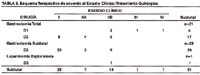

En la Tabla N° 10, se aprecia el análisis univariado de los factores que influencian la supervivencia en los pacientes con Linfoma Gástrico. Es de resaltar que los grupos son diferentes de acuerdo al factor evaluado, puesto que por ejemplo, no todos los pacientes tuvieron prueba de DHL, de la misma manera los esquemas terapéuticos fueron diferentes y no todos los pacientes recibieron o completaron los mismos. Los factores que tuvieron significancia estadística fueron los siguientes: el zubrod, el DHL, la remisión, el grado, el estadio clínico, el tratamiento y la localización. En el presente grupo, ni la edad ni el aspecto endoscópico tuvieron significancia estadística. El estadio clínico fue analizado agrupando el I-II versus el III-IV, de la misma manera, el grado fue analizado agrupando básicamente a los Linfomas MALT con relación a los Linfomas a células B, grande difuso.